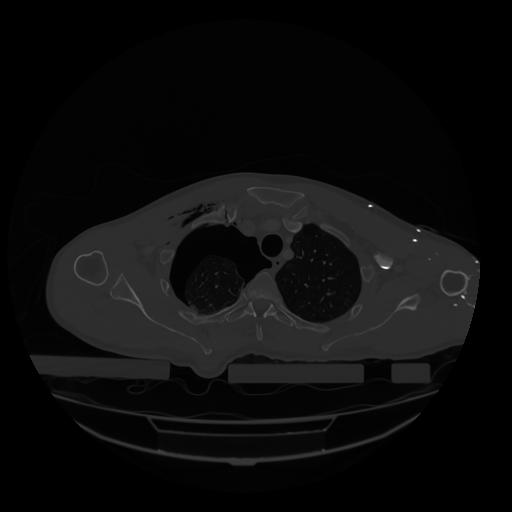

28 CUERPO,CE,Vol,2.0,CUERPO,,